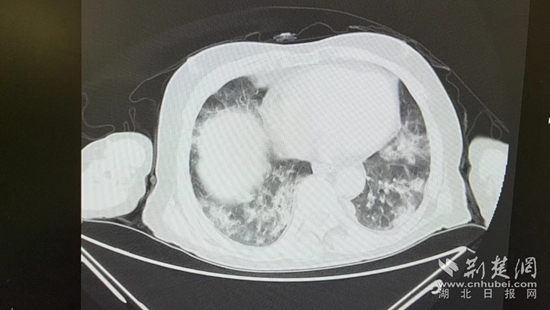

病情的突然惡化,會(huì)不會(huì)與近期的新冠病毒感染有關(guān)?雖然家屬反映,曾多次在家自測(cè)抗原正常,但徐濤還是力排眾議,說服老人進(jìn)行核酸檢測(cè)和肺部CT檢查。結(jié)果顯示核酸陽性,60%白肺,結(jié)合老人的表現(xiàn),這正是一例典型的老年人“沉默性肺炎”。

胸部CT片。通訊員 供圖